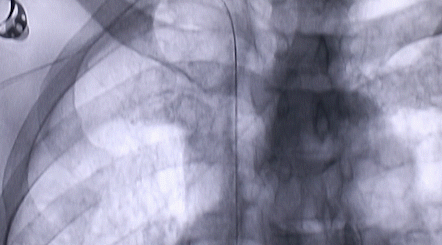

1月12日,西安國(guó)際醫(yī)學(xué)中心醫(yī)院心臟外科郭穎強(qiáng)主任團(tuán)隊(duì)成功為一名腹主動(dòng)脈閉塞、右側(cè)腎動(dòng)脈閉塞、左側(cè)腎動(dòng)脈重度狹窄、腹壁淺表動(dòng)脈側(cè)支循環(huán)形成、高血壓病3級(jí)(極高危組)合并閉塞性周圍動(dòng)脈粥樣硬化、急性腎功能不全的老年患者實(shí)施腎動(dòng)脈球囊擴(kuò)張 腎動(dòng)脈支架植入術(shù) 動(dòng)脈血栓抽吸術(shù) 髂動(dòng)脈開(kāi)通術(shù),治好了困擾患者多年的頑固性高血壓。患者目前康復(fù)良好,將于近日出院。

按照術(shù)前制定的方案,郭穎強(qiáng)主任和楊金保博士首先嘗試開(kāi)通閉塞的右腎動(dòng)脈,但由于血栓機(jī)化、鈣化嚴(yán)重,右腎動(dòng)脈難以開(kāi)通。遂謹(jǐn)慎擴(kuò)張狹窄的左腎動(dòng)脈,并成功植入一枚支架。之后經(jīng)過(guò)反復(fù)旋磨、抽吸,順利開(kāi)通髂動(dòng)脈,但腹主動(dòng)脈閉塞段仍難以擴(kuò)通。此時(shí),患者居高不下的血壓很快恢復(fù)到正常水平。